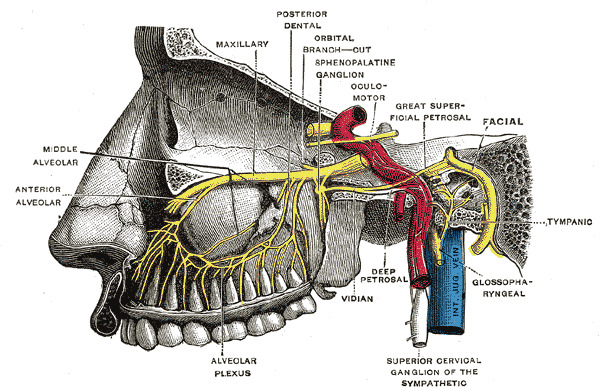

Maxillary a.

- Mandibular part

- Pterygoid part

- Pterygopalatine part

Info

Maxillary a.通過pterygoid muscle淺層,穿入pterygopalatine fossa

First part

- Ant. tympanic a.

- 進入 tympanic cavity,供應 tympanic membrane

- Middle meningeal

- 被Auriculotemporal n. 環繞

Second part

皆有(CN V3)伴行,除了Buccal n.為sensory,其為motor

- Ant./post. deep temporal a.

- Buccal a.

- Masseteric a.

- Pterygoid a.

Third part

皆有sensory 伴行,穿入pterygopalatine fossa

- Sphenopalatine a.

- 最終分支,進入 Sphenopalatine foramen,支配鼻竇

- Vidian a.

- Vidian n.

- maxillary tuberosity

- on alveolar bone